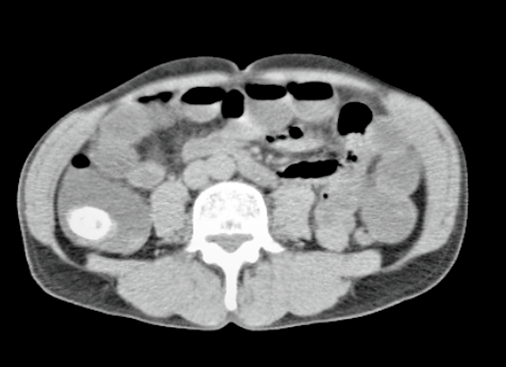

Ilustración 2 Tac con cálculo en válvula ileocecal

Fuente: Hospital de Especialidades Guayaquil “Doctor Abel Gilbert Pontón”.

Autor: Dr. Fernando Moncayo A.

Se presenta el caso de un paciente de sexo masculino, 68 años de edad, diabético, que debuta con dolor abdominal náuseas, vómitos, distensión abdominal intermitente con signo radiológico de obstrucción intestinal (edema interasas y signo de pilas de monedas), todos estos síntomas disminuyen luego de hidratación adecuada por lo cual se decide realizar tomografía computarizada la cual revela un cálculo de 2.5 a nivel de íleo terminal, por lo que se decide la intervención quirúrgica.

Entre los hallazgos tenemos; dilatación de asas intestinal con edema, cálculo de 2.5 cms de grosor en el interior de íleon terminal 5 cms de la válvula ileocecal, vesícula dura con paredes engrosadas y muy adherida al duodeno que al realizar la adherolisis se observa una comunicación entre la vesícula y el duodeno (fistula colecisto duodenal).